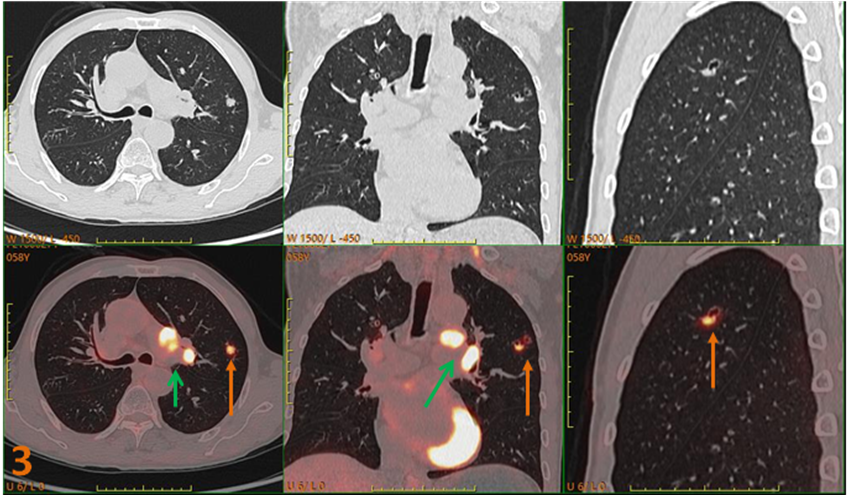

為明確原發灶行PET-CT進一步檢查(圖3、4)。PET/CT示:左肺上葉不規則囊性灶(SUVmax約5.3),左肺門、主動脈弓下高代謝病變(SUVmax約12.1);診斷為左肺上葉癌并多發轉移。

圖3、4. 左肺上葉不規則囊性灶(黃箭),SUVmax約5.3;左肺門、主動脈弓下高代謝病變(綠箭)SUVmax約12.1。